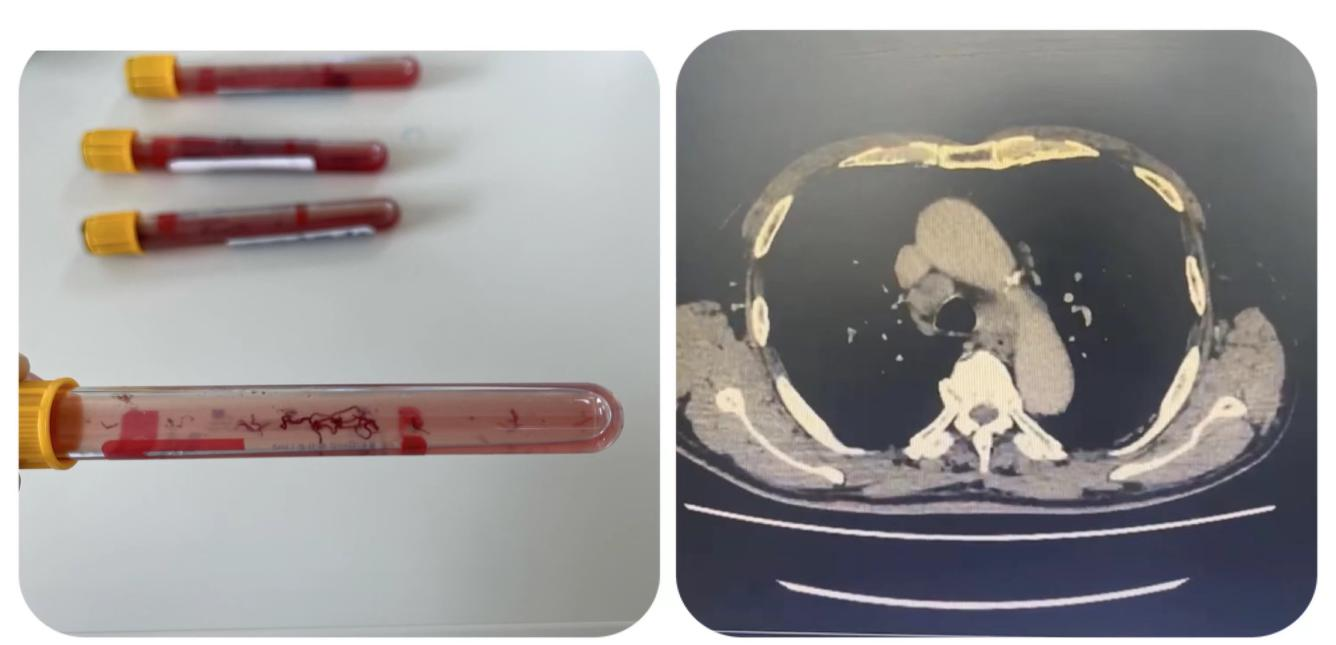

4月1日11时,顺利为患者进行检查:全麻下经喉罩进镜,见左肺及右肺各级支气管管腔通畅,黏膜光滑,镜下未见明显异常;更换超声支气管镜,依次探查探及4R组淋巴结、7组淋巴结肿大,长度分别为15.6mm、17mm,血供不丰富,两处给予针吸活检术,获得理想标本;手术历时40分钟,术中生命体征平稳,无不良反应。